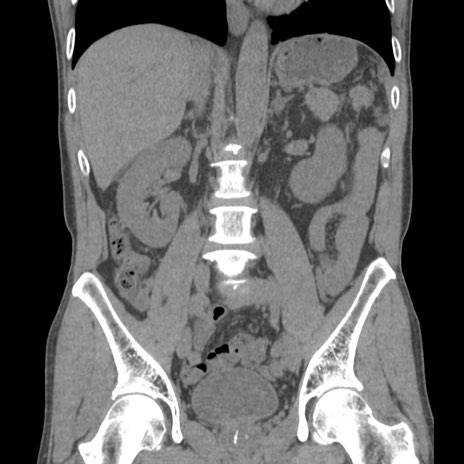

症例56 CT(冠状断像)

横断像